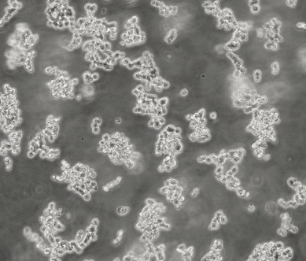

1. 形态特征:球形细胞,形成葡萄串状多细胞聚集体,悬浮生长特性。

1. 生长特性:细胞自然聚集成团,切勿人为分散